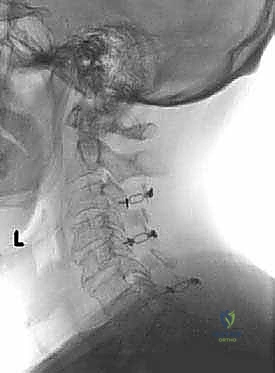

تُجرى عملية رأب الصفيحة العنقية تحت التخدير العام، وتستغرق عادةً ما بين ساعتين إلى أربع ساعات، اعتماداً على عدد المستويات الفقرية المتأثرة. يتبع الأستاذ الدكتور محمد هطيف بروتوكولاً جراحياً دقيقاً وصارماً لضمان أعلى نسب النجاح.

هناك تقنيتان رئيسيتان في رأب الصفيحة:

1. تقنية الباب المفتوح (Open-Door Laminoplasty - Hirabayashi): يتم قطع العظم بالكامل من جانب واحد، وعمل شق جزئي (مفصلة) من الجانب الآخر، ثم يُفتح العظم كالباب.

2. تقنية الباب الفرنسي المزدوج (French-Door Laminoplasty - Kurokawa): يتم شق العظم من المنتصف، وعمل مفصلات على كلا الجانبين، ويُفتح العظم من المنتصف كالباب المزدوج.

فيما يلي تفصيل لخطوات تقنية "الباب المفتوح" (الأكثر شيوعاً واستخداماً):

الخطوة 1: التحضير والتخدير ووضعية المريض

يتم إعطاء المريض تخديراً عاماً. يُوضع المريض على بطنه (وضعية الانبطاح - Prone Position) على طاولة عمليات خاصة. يتم تثبيت الرأس بعناية فائقة باستخدام جهاز تثبيت الجمجمة (Mayfield Tongs) لضمان عدم تحرك الرقبة ولو لمليمتر واحد أثناء الجراحة الدقيقة. يتم استخدام أجهزة مراقبة عصبية مستمرة (Neuromonitoring) لمراقبة وظائف الحبل الشوكي لحظة بلحظة طوال العملية.

الخطوة 2: الشق الجراحي والوصول للعظام

يُجري الدكتور هطيف شقاً جراحياً دقيقاً في منتصف الجزء الخلفي من الرقبة. يتم إبعاد عضلات الرقبة الخلفية برفق ولطف شديدين للوصول إلى الصفيحات العظمية (Laminae) للفقرات المستهدفة (غالباً من C3 إلى C6 أو C7).

الخطوة 3: إنشاء "المفصلة" (The Hinge)

باستخدام مثقاب جراحي دقيق (High-speed Burr) تحت التكبير الميكروسكوبي، يقوم الدكتور هطيف بنحت أخدود طولي على جانب واحد من الصفيحات العظمية (عند نقطة التقاء الصفيحة بالكتلة الجانبية). هذا